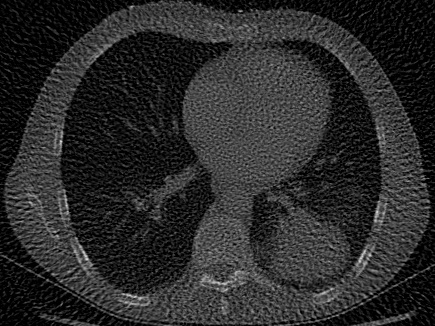

| Computed Tomography (CT) [28] | 2D | X-ray CT scan of a human chest, used to evaluate signal recovery in a classic underdetermined inverse problem. |

Computed Tomography (CT).

For CT experiments, we train models on a real chest CT slice from the dataset in Clark et al. [28], which was also used in WIRE [16]. The training data was 100 projection measurements of the original 326435 chest CT slice, forming a 100435 sinogram equivalent to approximately 30% of the total pixel count in the original image. Since this inverse problem is inherently underdetermined, we apply TV regularization in our Grid model. The TV hyperparameter was tuned using the classic Shepp-Logan phantom image [37] as a reconstruction target.